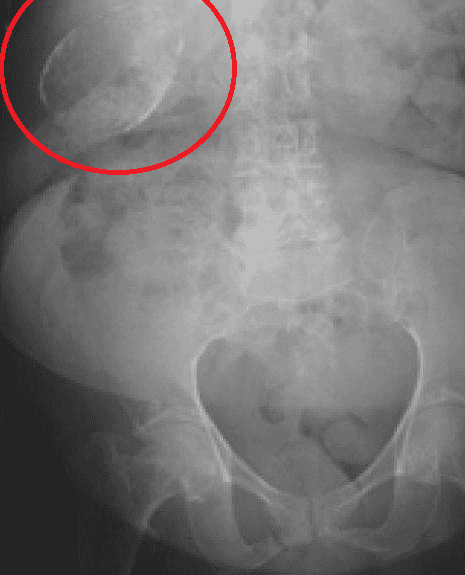

Porcelain gallbladder is a calcification of the gallbladder believed to be brought on by excessive gallstones, although the exact cause is not clear. As with gallstone disease in general, this condition occurs predominantly in overweight female patients of middle age. It is a morphological variant of chronic cholecystitis. Inflammatory scarring of the wall, combined with dystrophic calcification within the wall transforms the gallbladder into a porcelain-like vessel. Removal of the gallbladder (cholecystectomy) is the recommended treatment. Symptoms are similar to gallstones and can include abdominal pain (especially after eating), jaundice, and vomiting. Porcelain gallbladder can also be asymptomatic and discovered on imaging obtained for a different reason. The assertion that porcelain gallbladder increases the incidence of gallbladder cancer is widely taught in medical schools but is based on studies from 1931 and 1962. A prominent study aid for surgical residents even states that the risk of cancer in a porcelain gallbladder is 15%. The precise nature of the association between gallbladder cancer and porcelain gallbladder is uncertain. Two articles published in 2001 examined the association between cancer of the gallbladder and calcified gallbladder. The first study reviewed 10,741 cholecystectomies and found that the 88 patients with gallbladder cancer did not have calcified gallbladders while the 15 patients with porcelain gallbladders did not have gallbladder cancer. The second study reviewed 25,900 gallbladder specimens and found 150 patients with cancer and 44 patients with calcified gallbladders of two types (intramural calcification and selective mucosal calcification). The selective mucosal calcification group showed a 7% incidence of cancer with a significant odds ratio of 13.89. An article published in 2013 reviewed 111 studies and found 340 patients with gallbladder wall calcification showed a 21% overall rate of gallbladder malignancy; however, when studies with obvious selection bias were excluded the rate of gallbladder malignancy fell to 6%.